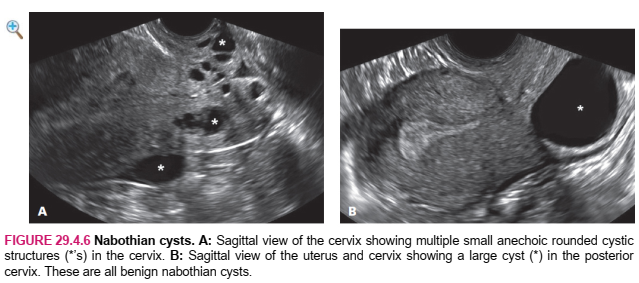

Cysts in the cervix are most often nabothian cysts, which are benign mucus-filled structures occurring within the substance of the cervix and abutting the endocervical canal. These are common and, unless large or infected, are clinically irrelevant.

Cervical lymphoma appears as a hypoechoic cervical mass with a lobular contour (Figure 29.4.5). The lesion, like other cervical malignancies, has abundant vascularity. Nabothian cysts are typically sonolucent, unilocular cysts of varying sizes (Figure 29.4.6) within the cervix. They occasionally contain debris. Cervical polyps arise in the endocervical canal and appear as discrete echogenic lesions (Figure 29.4.7) and, like endometrial polyps, often have a feeding vessel. Endometrial polyps may be seen within the cervical canal if they prolapse. In such cases, the polyp appears as a well-defined echogenic lesion with a vascular stalk extending into the uterine cavity (see Section 30.1).

HÌNH 29.4.6 Nang naboth. A: Mặt cắt Sagittal qua cổ tử cung cho thấy nhiều cấu trúc nang tròn nhỏ không dội âm (* ’) trong cổ tử cung. B: Mặt cắt Sagittal tử cung và cổ tử cung thấy một nang lớn (*) ở phía sau cổ tử cung. Đây đều là những nang naboth lành tính.